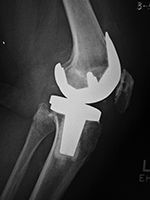

Posterior cruciate substituting total knee prosthesis and patellar resurfacing. |

| 68 year-old woman treated for severe left knee osteoarthritis |

Note the large distal femoral box. There is a surgical drain in the suprapatellar space. |